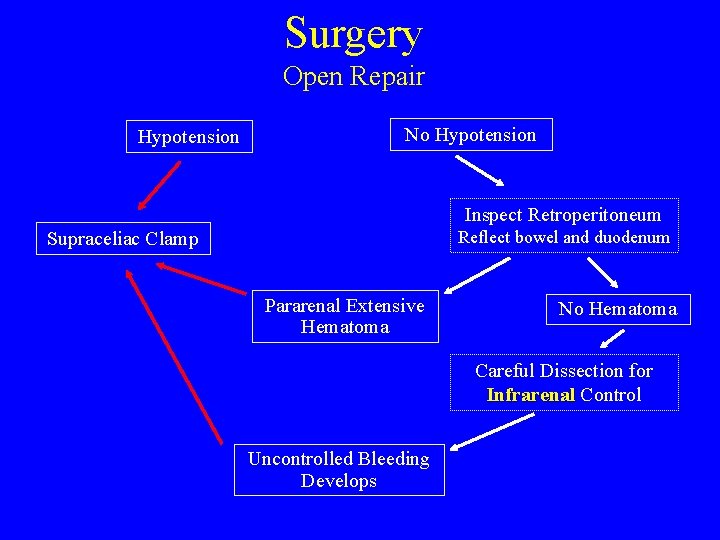

Surgery Open Repair Hypotension No Hypotension Inspect Retroperitoneum Supraceliac Clamp Reflect bowel and duodenum Pararenal Extensive Hematoma No Hematoma Careful Dissection for Infrarenal Control Infrarenal Uncontrolled Bleeding Develops